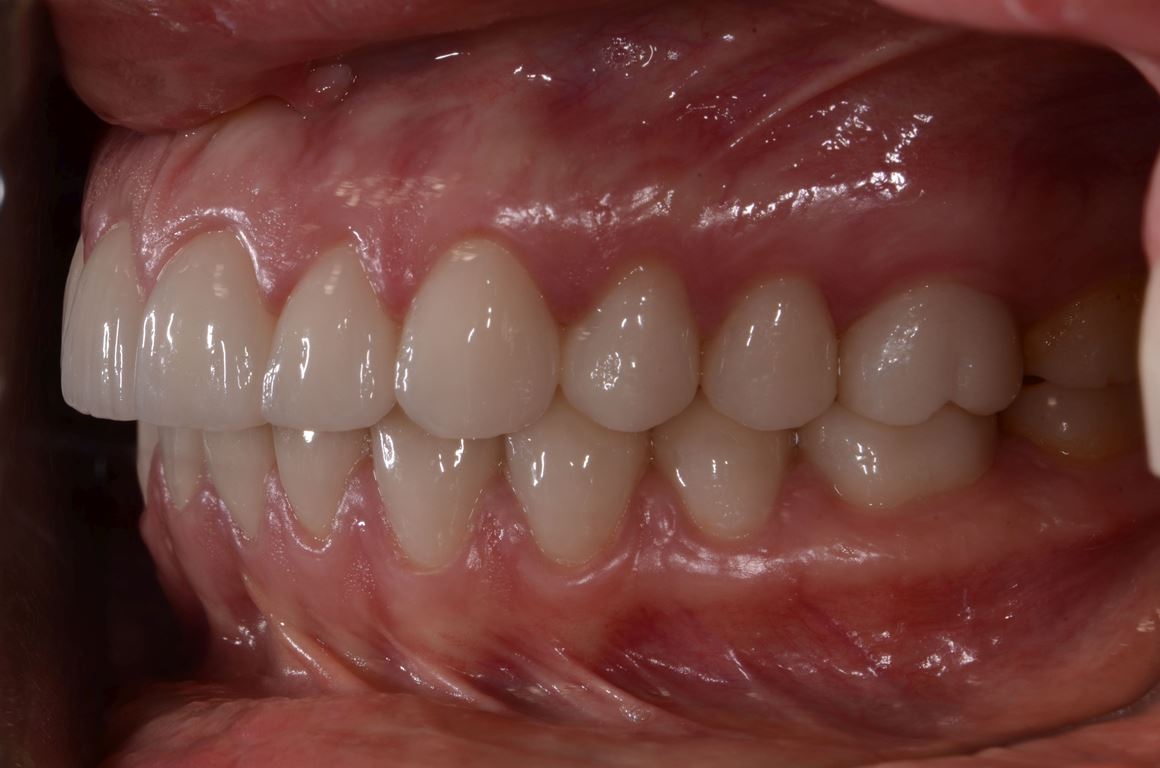

W pierwszym etapie diagnostycznym wykonano zdjęcia zewnątrz- i wewnątrzustne (ryc. 1-12).

Ryciny 39-50 przedstawiają stan po zakończeniu leczenia.